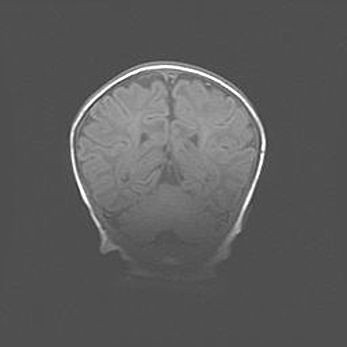

Церебральная ишемия II.

Возраст: 5 дней

Вес: 3400 г

Пол: женский

Окружность головы: 35 см

Срок гестации: 39 недель

Церебральная ишемия – это заболевание, характеризующееся недостаточностью (гипоксией) либо полным прекращением (аноксией) снабжения мозга кислородом по причине закупорки одного или нескольких сосудов. Это приводит к  что метаболическим расстройствам различной степени тяжести в тканях головного мозга, развитию коагуляционных некрозов и гибели нейронов.